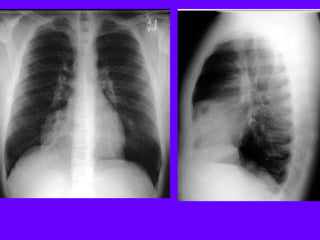

Left Upper Lobe Consolidation

Density in the left upper lung field

Loss of silhouette of left heart margin

Density in the projection of LUL in lateral view

Air bronchogram in PA view

No significant loss of lung volume